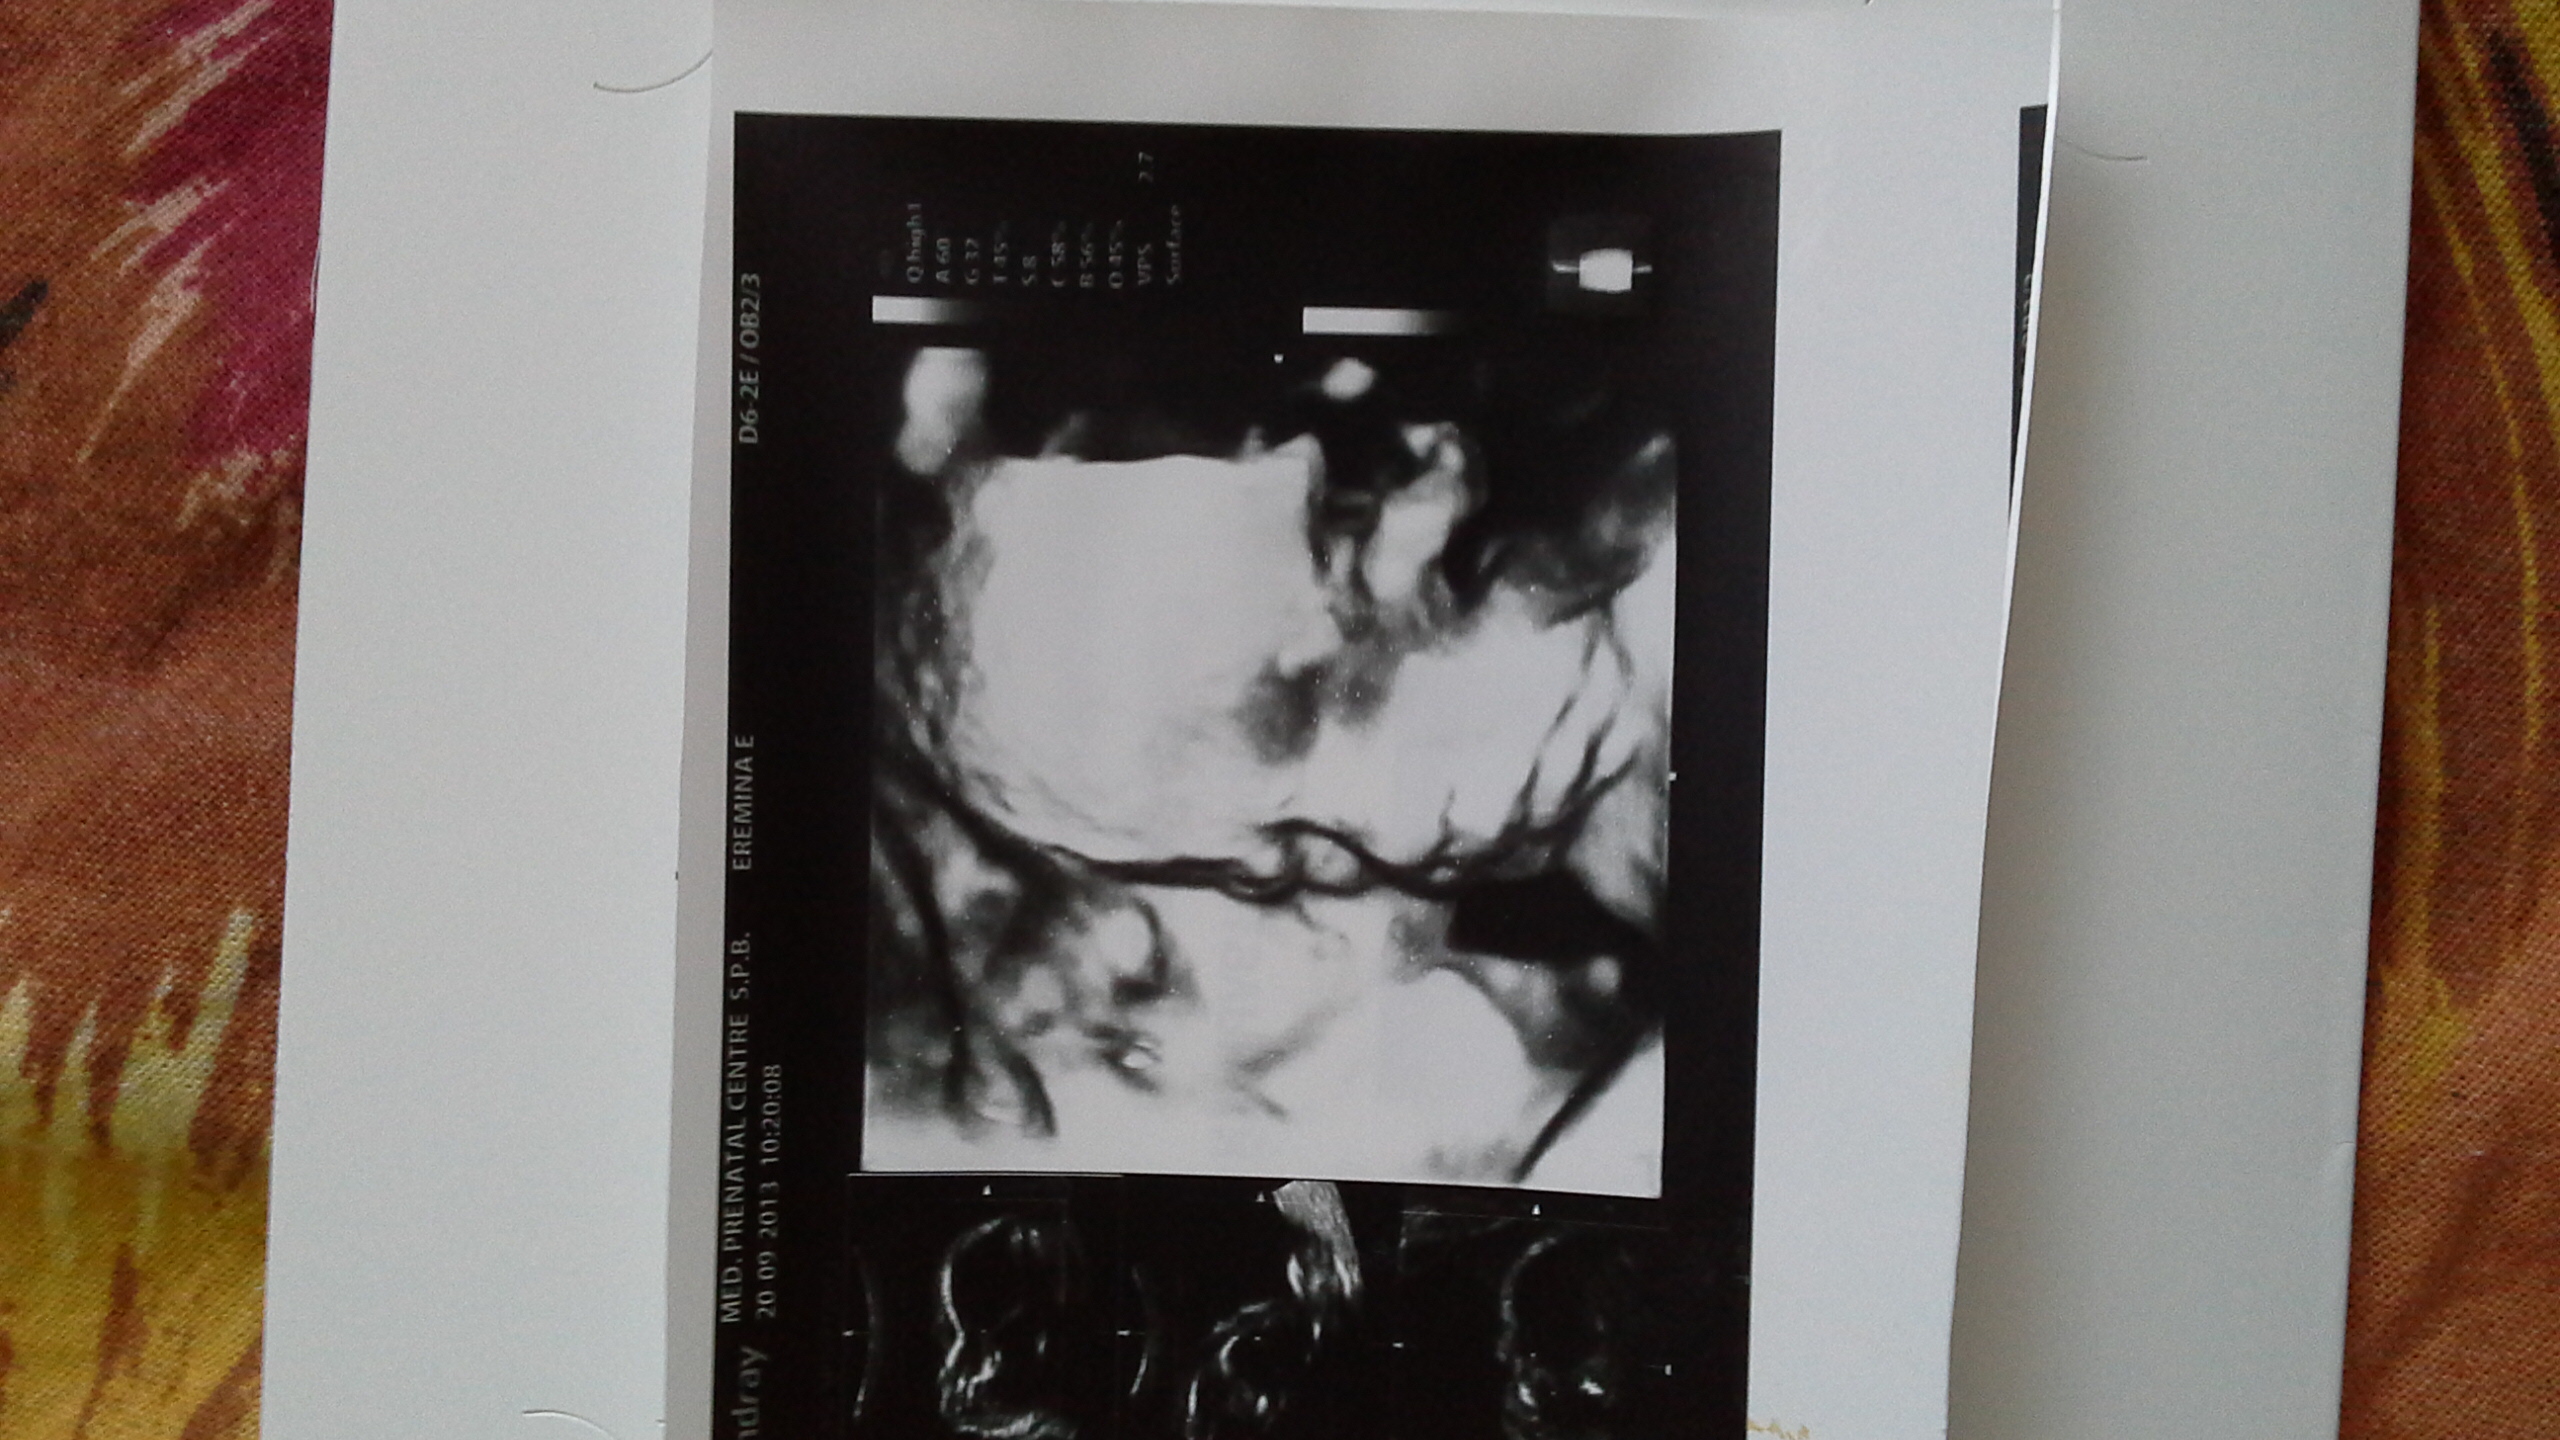

первая фото 24 нед.